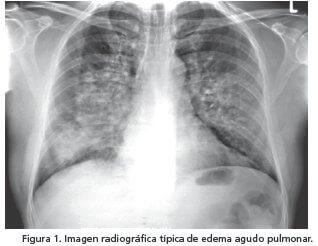

Radiografía de tórax:

Es característico de un edema agudo de pulmón, el patrón alveolar de Felson, el cual consiste en nódulos que confluyen, de aspecto algodonosos, con bordes mal definidos, de distribución lobar o segmentaria. A su vez, hay otros hallazgos que se pueden observar en la radiografía de tórax, pero estos están relacionados con el origen del edema agudo de pulmón, como:

Cardiomegalia.

Edema intersticial.

Líneas B de Kerley: Estas son líneas cortas, rectas y de sentido horizontal que pueden encontrarse en los senos costofrénicos.

Líneas A de Kerley: Estas también son rectas, pero más largas y se encuentran apuntando hacia el hilio pulmonar, por lo que son verticales.

Derrame pleural.

Redistribución vascular.